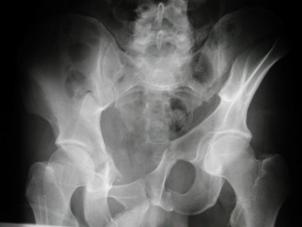

TRAUMATISMELE PELVIENE

Banda de stabilizare Dallas Fractura de bazin. Radiografie in

incidenta AP

Fractura de bazin

. Radiografie in incidenta AP Fractura de spina